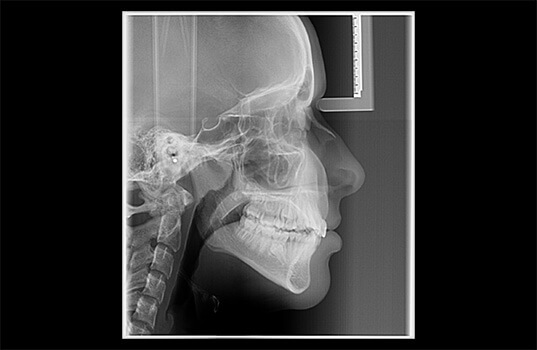

A Teleradiografia Lateral/Frontal é uma radiografia que serve para ver os ossos do crânio, mandíbula e pescoço. É usada na odontologia para descobrir problemas como fraturas, tumores, cistos, infecções, entre outros. Ela também é usada para planejar cirurgias na boca, avaliar o desenvolvimento de tratamentos como a colocação de implantes dentários e dar uma visão geral das estruturas ósseas e dentárias.

Também é comum que a Teleradiografia Lateral/Frontal seja combinada com outros exames radiográficos, como a panorâmica, por exemplo, para obter uma visão mais completa das estruturas ósseas e dentárias.